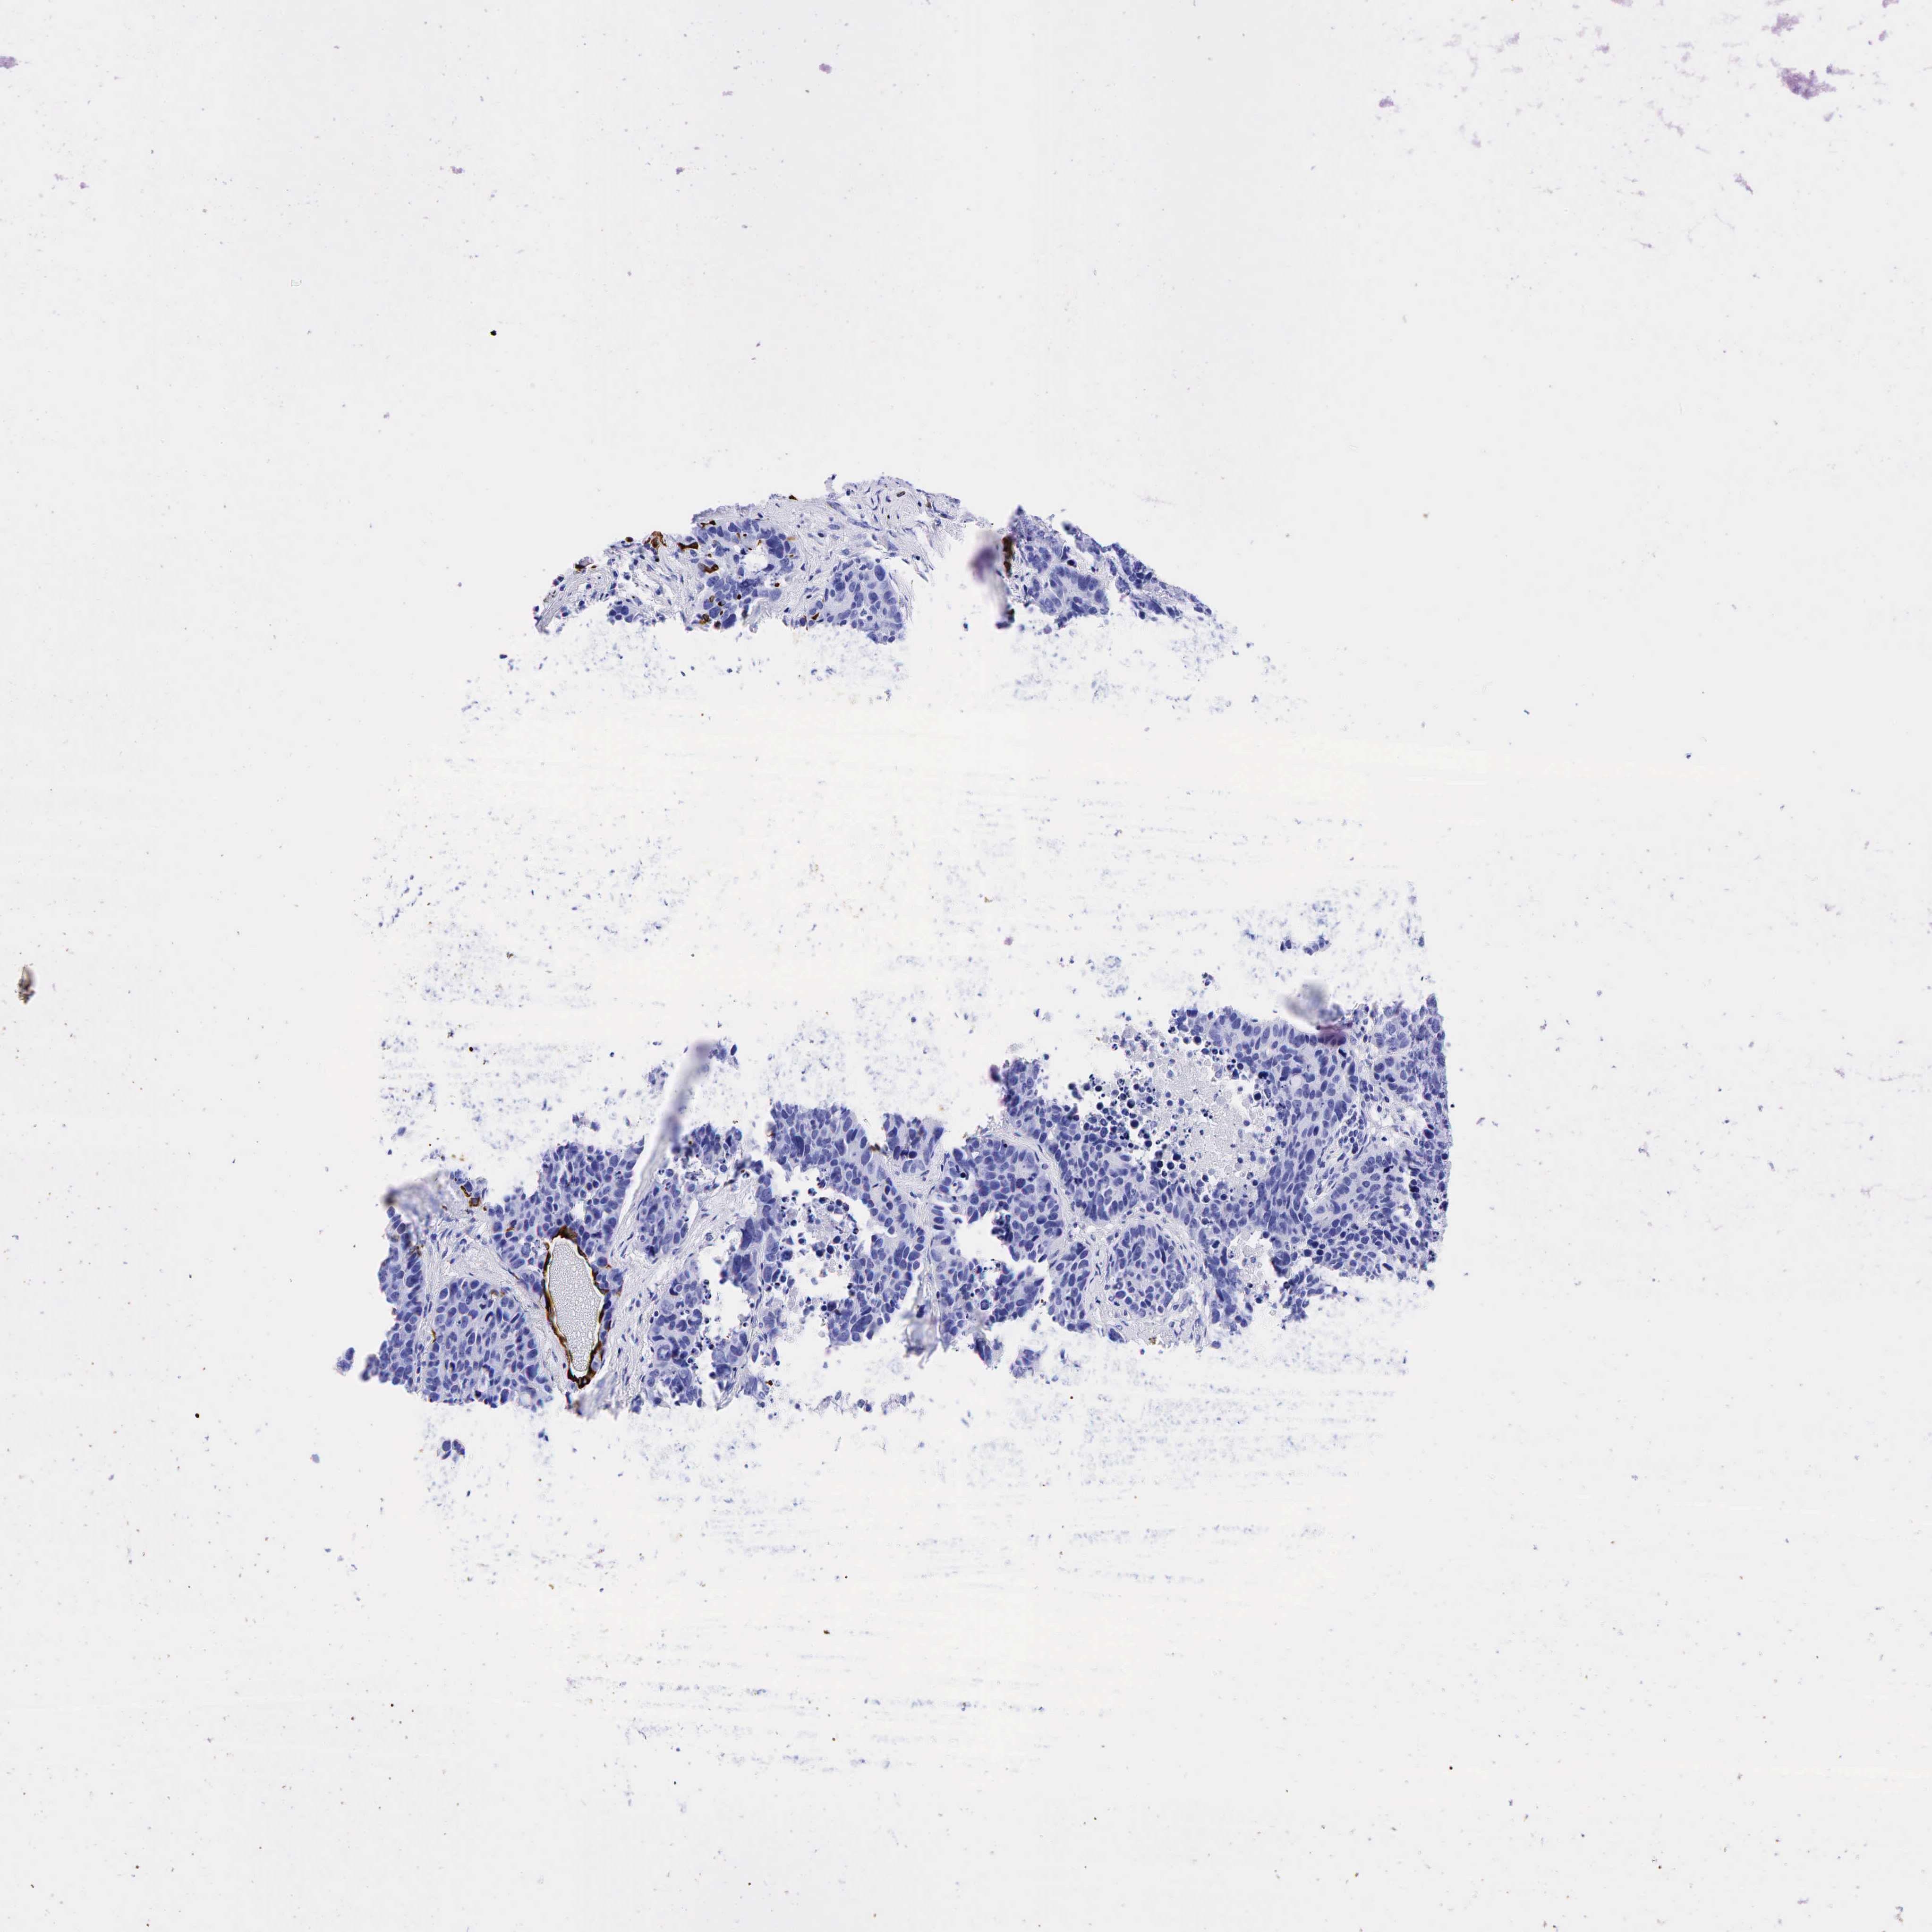

KRT19